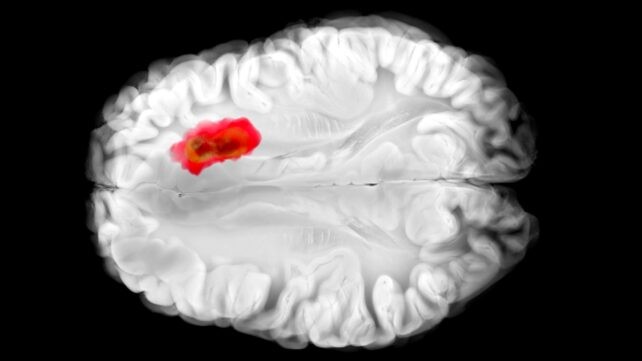

Hydralazyna od dekad stosowana jest w leczeniu nadciśnienia, choć do dziś nie było jasne, jak dokładnie działa. Teraz najnowsze badanie z Uniwersytetu Pensylwanii rzuca światło na mechanizm i otwiera intrygujące powiązanie z glejoblastomą mózgu. Przyglądając się bliżej wpływowi hydralazyny na komórki ludzkie i mysie, zespół badawczy z Uniwersytetu w Pensylwanii doszedł do wniosku, że lek ten blokuje określony enzym o nazwie 2-aminoethanethiol dioxygenase (ADO). Ten sam enzym, jak się okazuje, prawdopodobnie odgrywa rolę w agresywnych nowotworach mózgu – glejoblastomach. To nowe zrozumienie hydralazyny mogłoby otworzyć drogę do nowych terapii przeciwko nowotworom, a także poprawić skuteczność leku w jego obecnych zastosowaniach. Powiązane: Serotonina mogłaby odgrywać nieoczekiwaną rolę w raku, odkrywają naukowcy „Hydralazyna jest jednym z najstarszych leków rozszerzających naczynia, jakie kiedykolwiek opracowano, i nadal jest leczeniem z wyboru w preeklampsji – nadciśnieniowym zaburzeniu, które odpowiada za 5–15 procent zgonów matek na całym świecie,” mówi lekarz-naukowiec Kyosuke Shishikura z University of Pennsylvania. „Wyszła z epoki 'pre-target' odkrywania leków, gdy badacze polegali na tym, co widzieli u pacjentów, a dopiero później próbowali wyjaśnić biologiczne mechanizmy stojące za tym.” „ADO jest uważany za 'alarmowy dzwonek', który ostrzega organizm przed spadającymi poziomami tlenu. Wywołuje on kaskadę reakcji, zacieśnia naczynia krwionośne poprzez niszczenie białek RGS (regulatorów sygnalizacji G‑białek).” „Poprzednie badania pokazały, że guzy glejoblastomy często mają wysoki poziom ADO, wykorzystując go do produkcji związku o nazwie hipotauryna, która pomaga komórkom nowotworowym się rozprzestrzeniać, przetrwać dłużej i tolerować stres.” „Jednak przed tym badaniem nie były znane inhibitory ADO.” Hydralazyna skutecznie tłumi ADO, zespół stwierdził: białka RGS nie są atakowane, naczynia krwionośne nie są zwężane, a ciśnienie krwi spada. W eksperymentach na ludzkich komórkach glejoblastomy hydralazyna powstrzymała wzrost guza poprzez blokowanie ADO. To bardzo wczesne dni – skutki hydralazyny jeszcze trzeba przetestować w ludziach z glejoblastomą w badaniach klinicznych – ale to obiecujące wyniki, które mogą otworzyć drogę do ograniczenia rozprzestrzeniania się tych notorycznie trudnych do leczenia guzów mózgu. Nowo odkryty mechanizm wyjaśnia także, dlaczego hydralazyna jest skutecznym leczeniem preeclampsji, wysokiego ciśnienia krwi u ciężarnych kobiet. Oznacza to, że lek może być lepiej projektowany i personalizowany, aby ograniczyć skutki uboczne i poprawić wyniki u pacjentów znajdujących się w największym ryzyku,” mówi chemik Megan Matthews z University of Pennsylvania. Te odkrycia oznaczają, że lepsze leki na nadciśnienie i rak mózgu mogą być teraz opracowywane, starannie balansując konieczność trafienia w konkretne ścieżki w komórkach przy jednoczesnym minimalizowaniu szkód dla zdrowych tkanek. Ponieważ hydralazyna jest już szeroko stosowana, zrozumienie jej mechanizmu działania daje naukowcom pewien punkt wyjścia, jeśli chcą opracować więcej terapii opartych na tym związku. W przyszłości może uda się usunąć jedną z kluczowych obron glejoblastomy, dołączając do terapii już opracowywanych. „Rzadko zdarza się, że stary lek na choroby serca uczy nas czegoś nowego o mózgu,” mówi Matthews, „ale właśnie tego mamy nadzieję znaleźć więcej – niezwykłe powiązania, które mogą wróżyć nowe rozwiązania.” Badanie opublikowano w Science Advances.

Badanie prowadzone przez zespół z University of Pennsylvania przeanalizowało wpływ hydralazyny na komórki ludzkie i mysie. Doszli do wniosku, że lek ten blokuje enzym 2-aminoethanethiol dioxygenase (ADO). Ten enzym, jak się okazuje, jest związany z agresywnymi glejoblastomami. Hydralazyna skutecznie tłumi ADO, co prowadzi do braku ataków na białka RGS, nienaruszonych naczyń krwionośnych i spadku ciśnienia krwi. W eksperymentach na ludzkich komórkach glejoblastomy hydralazyna powstrzymała wzrost guza poprzez blokowanie ADO. To dopiero początek – efekty hydralazyny muszą zostać zweryfikowane w badaniach klinicznych na pacjentach z glejoblastomą, jednak te wyniki są obiecujące i mogą otworzyć drogę do ograniczenia rozprzestrzeniania się tych trudnych do leczenia guzów mózgu.

ADO jest uważany za „alarmowy dzwonek”, ostrzegający organizm przed spadającymi poziomami tlenu. Wywołuje on kaskadę reakcji, powodując zwężanie naczyń krwionośnych poprzez niszczenie białek RGS (regulatorów sygnalizacji G‑białek). Guz glejoblastoma często ma wysokie stężenie ADO, co pozwala mu produkować hipotaurynę, związek, który pomaga komórkom nowotworowym rozprzestrzeniać się, przeżyć dłużej i tolerować stres. Hydralazyna tłumi ADO, co prowadzi do braku atakowania białek RGS i spadku ciśnienia krwi. W eksperymentach na ludzkich komórkach glejoblastomy lek powstrzymał wzrost guza poprzez blokowanie ADO. Nowo odkryty mechanizm wyjaśnia także, dlaczego hydralazyna jest skutecznym leczeniem preeplampsii – i otwiera drogę do lepszego projektowania leków i spersonalizowanych terapii. Badanie zostało opublikowane w Science Advances.